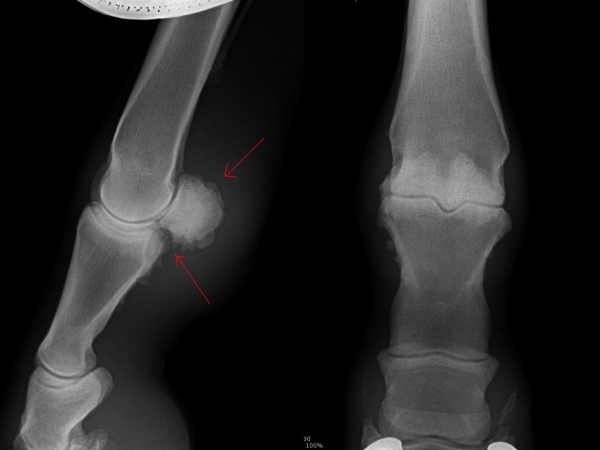

Čip ve spěnkovém kloubu na pánevní končetině

rentgenologické vyšetření

Fragment na spěnkové kosti